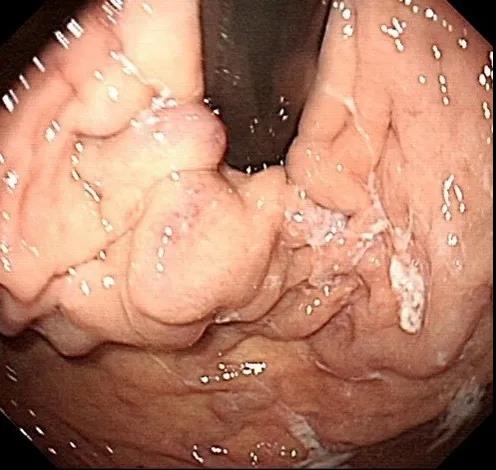

入院后予禁食、抑酸、補液、輸血處理,與家屬溝通,完善胃鏡檢查,結(jié)果示胃底巨大曲張靜脈團、門脈高壓性胃病。蓋偉主任考慮胃底靜脈團大、靜脈壓力高,合并分流道的可能性越大,且多數(shù)為胃脾分流,應首先完善門靜脈血管成像檢查,以明確血管情況。成像檢查結(jié)果符合食管胃底靜脈曲張CT表現(xiàn),胃底血管部分與脾靜脈相交通。

術前胃鏡及血管成像